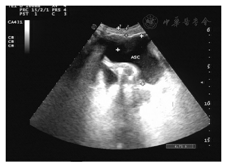

病例2王某,女,71岁,因卵巢癌晚期合并大量腹水于2014年11月25日入院。患者约于1年前被诊断为卵巢癌,行腹腔镜手术(术式不详),经过6次化学药物治疗。于4个月前出现腹腔积液。本次入院主要是因为大量腹水至卧床、呼吸困难,时有腹部疼痛,见图3。入院后的第5日,我们给予腹部穿刺、置入微管持续引流,每日控制引流1 500 ml,引流半月腹水无减少情况,多为渗出性,腹水中有癌细胞检出,患者虚弱。于入院后第20日开始给予三氧水腹腔内灌注引流,每日2次,每次100 ml,灌注后闭管2 h后开放引流。3 d后引流量开始减少,连续7 d后,每日开放引流,24 h腹水量减少至200 ml,渗出液中癌细胞数、红细胞数明显减少。于引流后第9日患者夜间活动时引流管脱落,未再引流。隔日复查B型超声仅为少量腹腔液体,好转出院,见图4、图5。